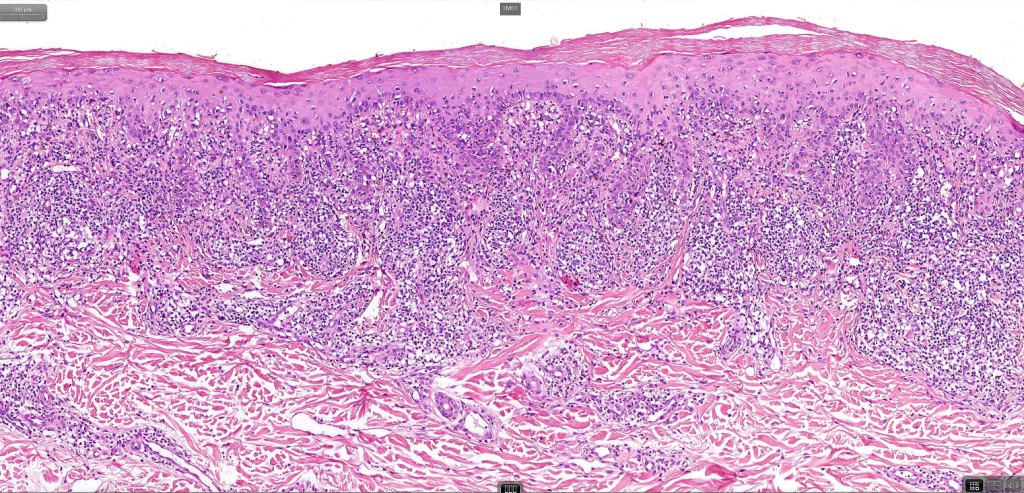

•Hyperkeratosis +/- parakeratosis

•Wedge-shaped hypergranulosis

•Generally irregular (sometimes saw-tooth) acanthosis but may show broad acanthosis

•Interface change

•Conspicuous cytoid bodies

•Pigment incontinence

•Band-like or perivascular infiltrate of lymphocytes, histiocytes with occasional eosinophils & plasma cells